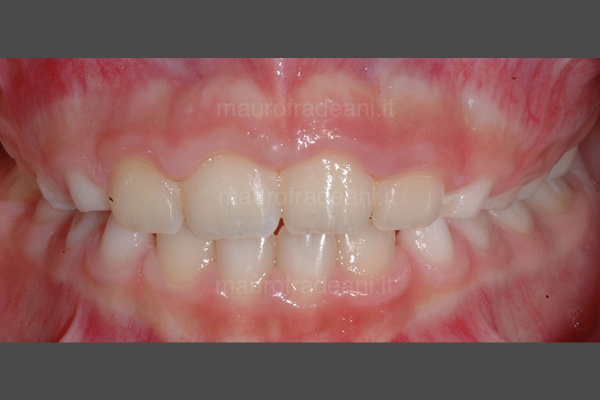

Early orthodontics: malocclusion and tooth crowding

Go to gallery